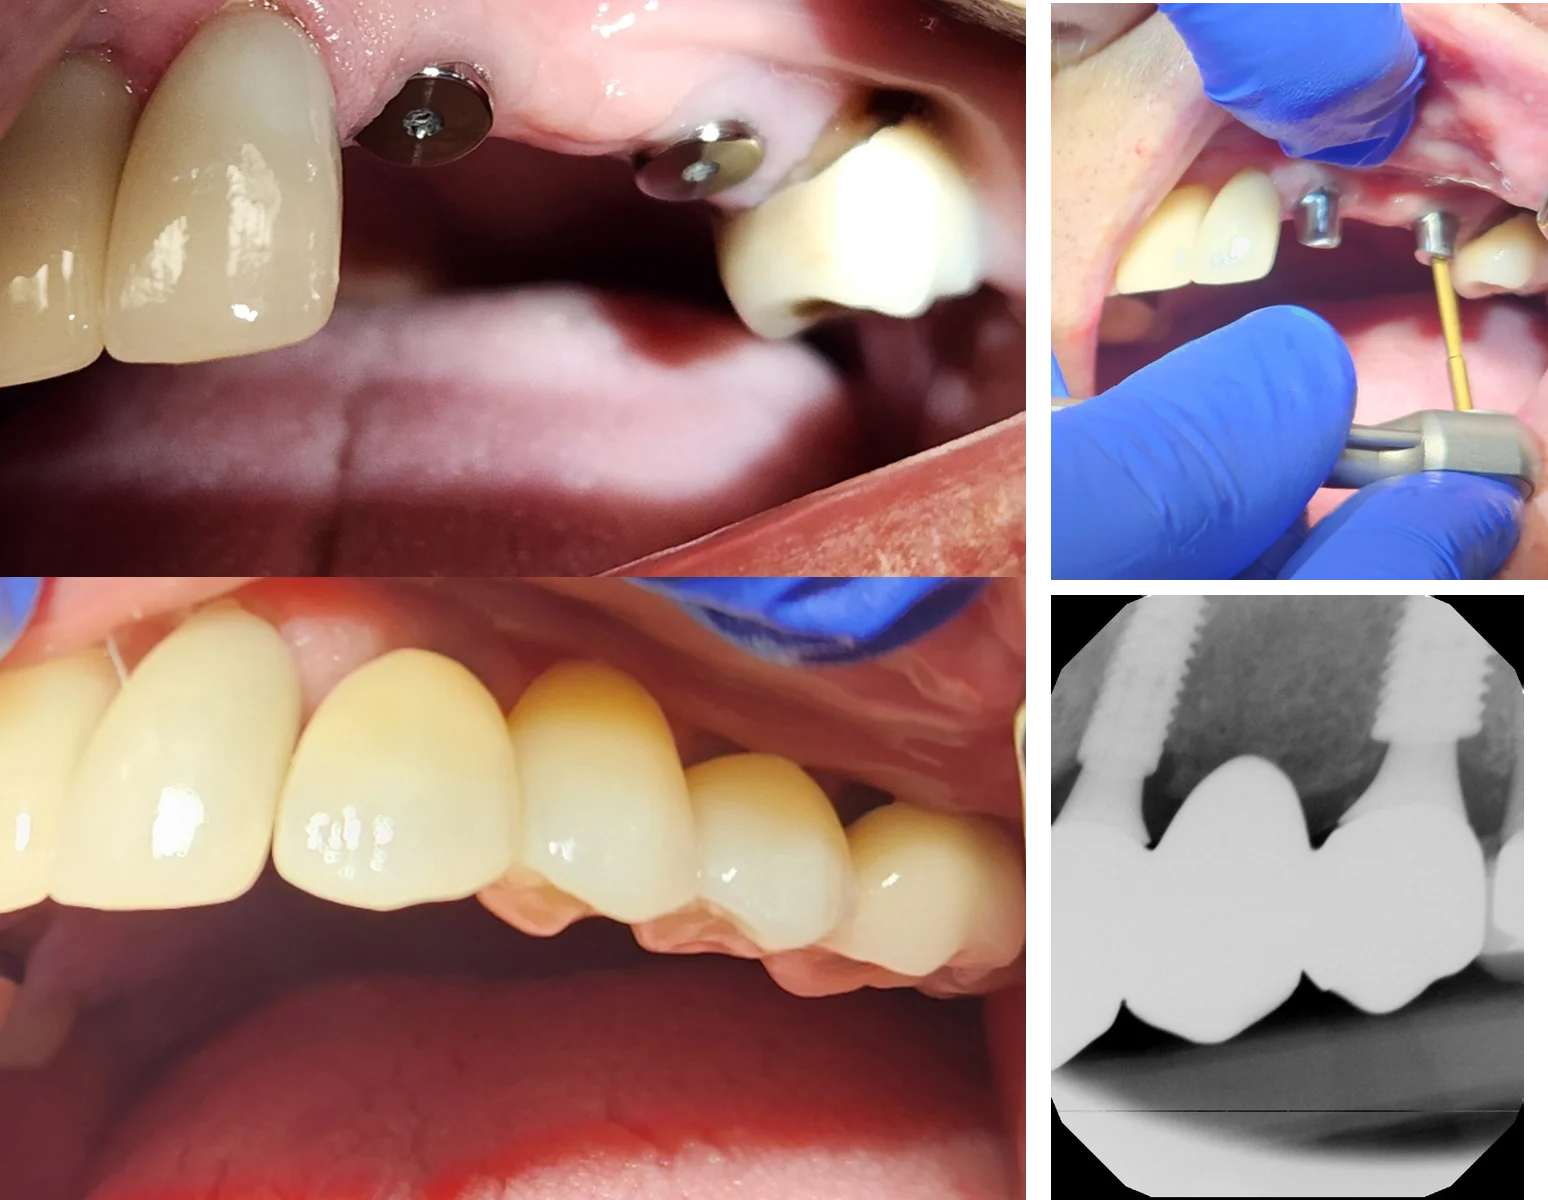

Custom Crown & Final Tooth

Crown placement

Once the implant is fully integrated, we take a digital scan and design a custom-milled abutment and crown. The final tooth is made to fit your bite and blend with your smile.